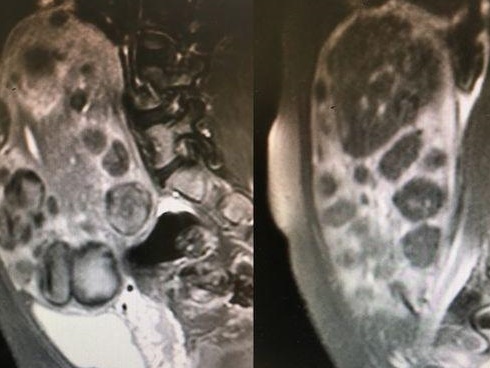

Một trong những bức ảnh gây bão mạng

Khuôn mặt "khó ở" khi được chụp X-quang

Cô bé này cũng không hiểu chuyện gì đang xảy ra với mình

Một bức ảnh hài hước khác của các bé